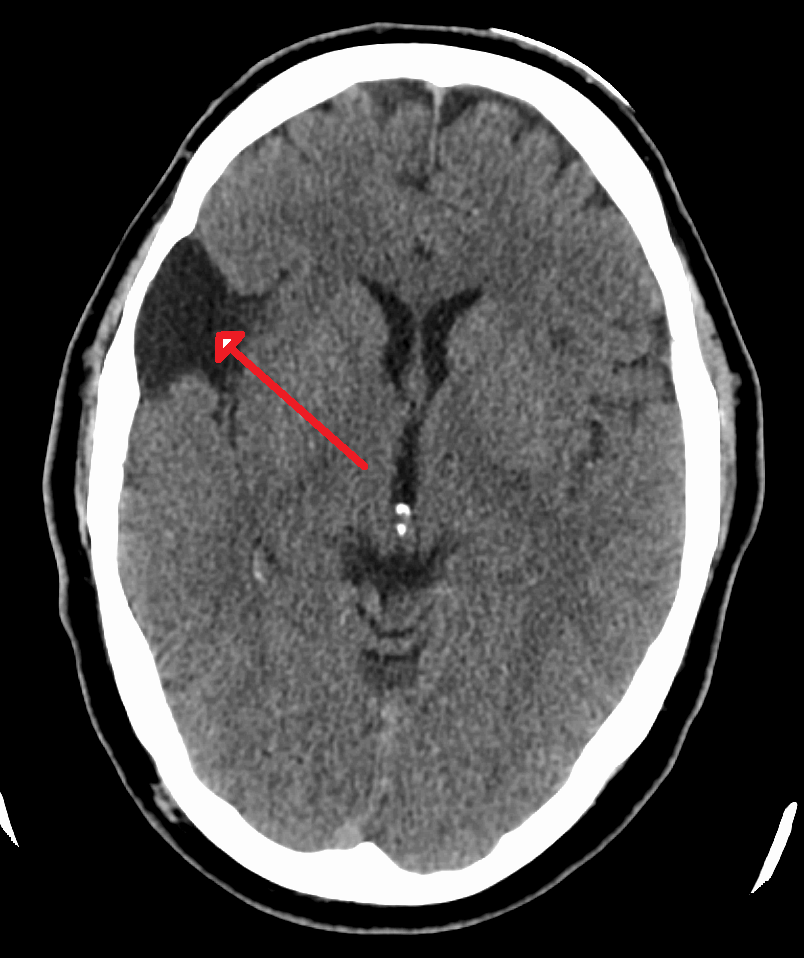

진단은 주로 MRI로 이루어진다. 지주막낭종은 다른 임상적 이유로 MRI를 촬영하는 과정에서 우연히 발견되는 경우가 많다.[9] 실제적으로 증상이 있는 지주막낭종을 진단하려면 증상이 나타나야 하며, 이 질환을 가진 많은 환자는 평생 증상이 나타나지 않는다.

지주막낭종 진단은 주로 MRI로 이루어진다.[9] 지주막낭종은 다른 임상적 이유로 MRI를 촬영하는 과정에서 우연히 발견되는 경우가 많다.[9] 실제적으로 증상이 있는 지주막낭종을 진단하려면 증상이 나타나야 하며, 이 질환을 가진 많은 환자는 평생 증상이 나타나지 않는다.